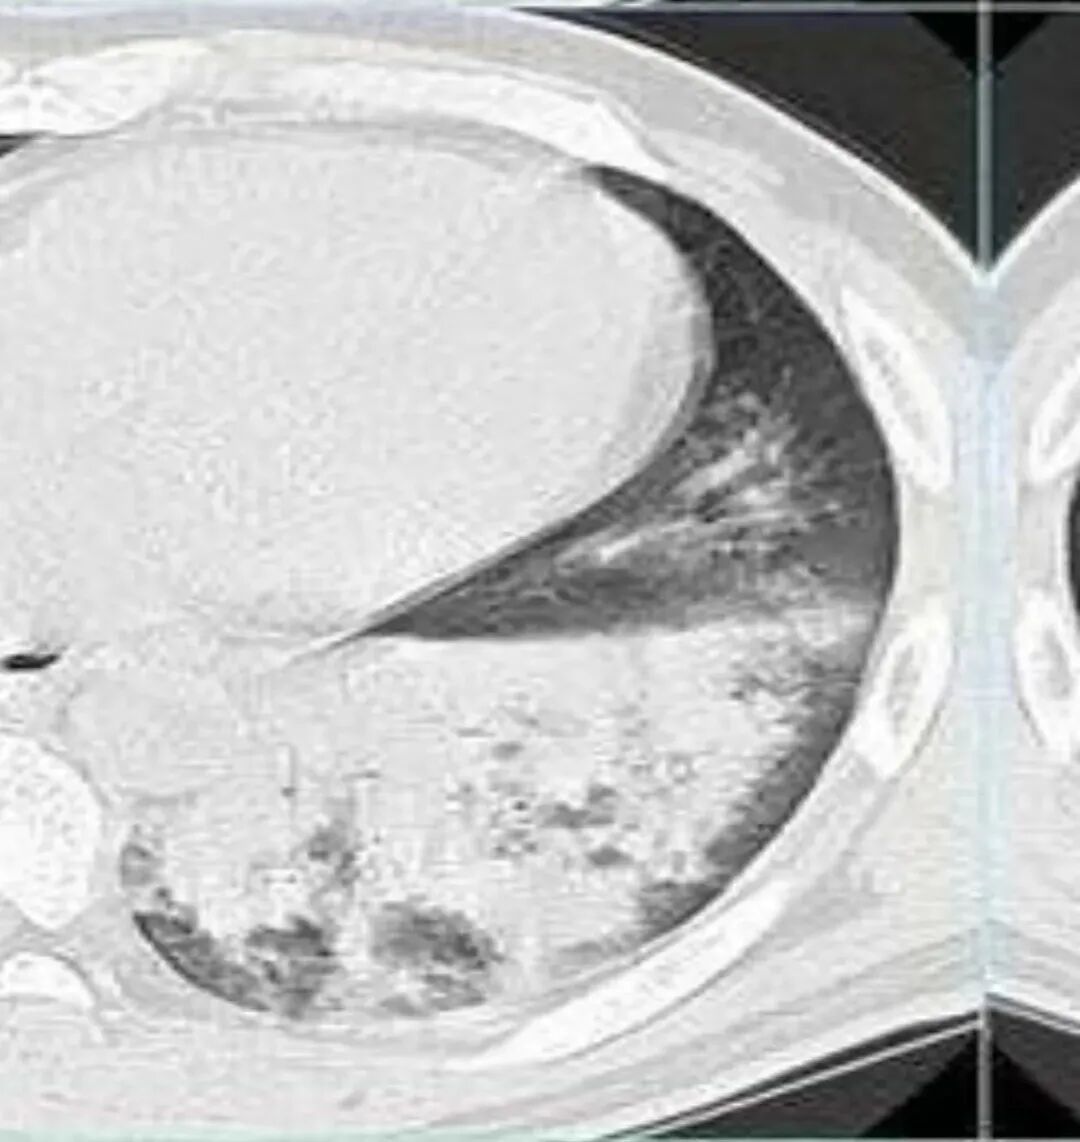

治疗后复查

今天的病例复查很符合金葡菌

左下肺的囊腔呈簇状分布

这个区域应该是外侧最重的,但是没有看到空洞。二元论也可以,单纯从影像看金葡也不一定都是小叶性改变的,肺泡性改变也可以,从病史看,可能病毒合并金葡。

这个病史发热三天,胸痛可能是后面金葡引起的,这些不一定是金葡,可能就有基础疾病,合并的这个。真正的病史就是金葡引起,病史就发热三天,近期加重,这三天就是金葡的改变。

怀疑这个可能是在治疗过程中,改变了影像学表现。